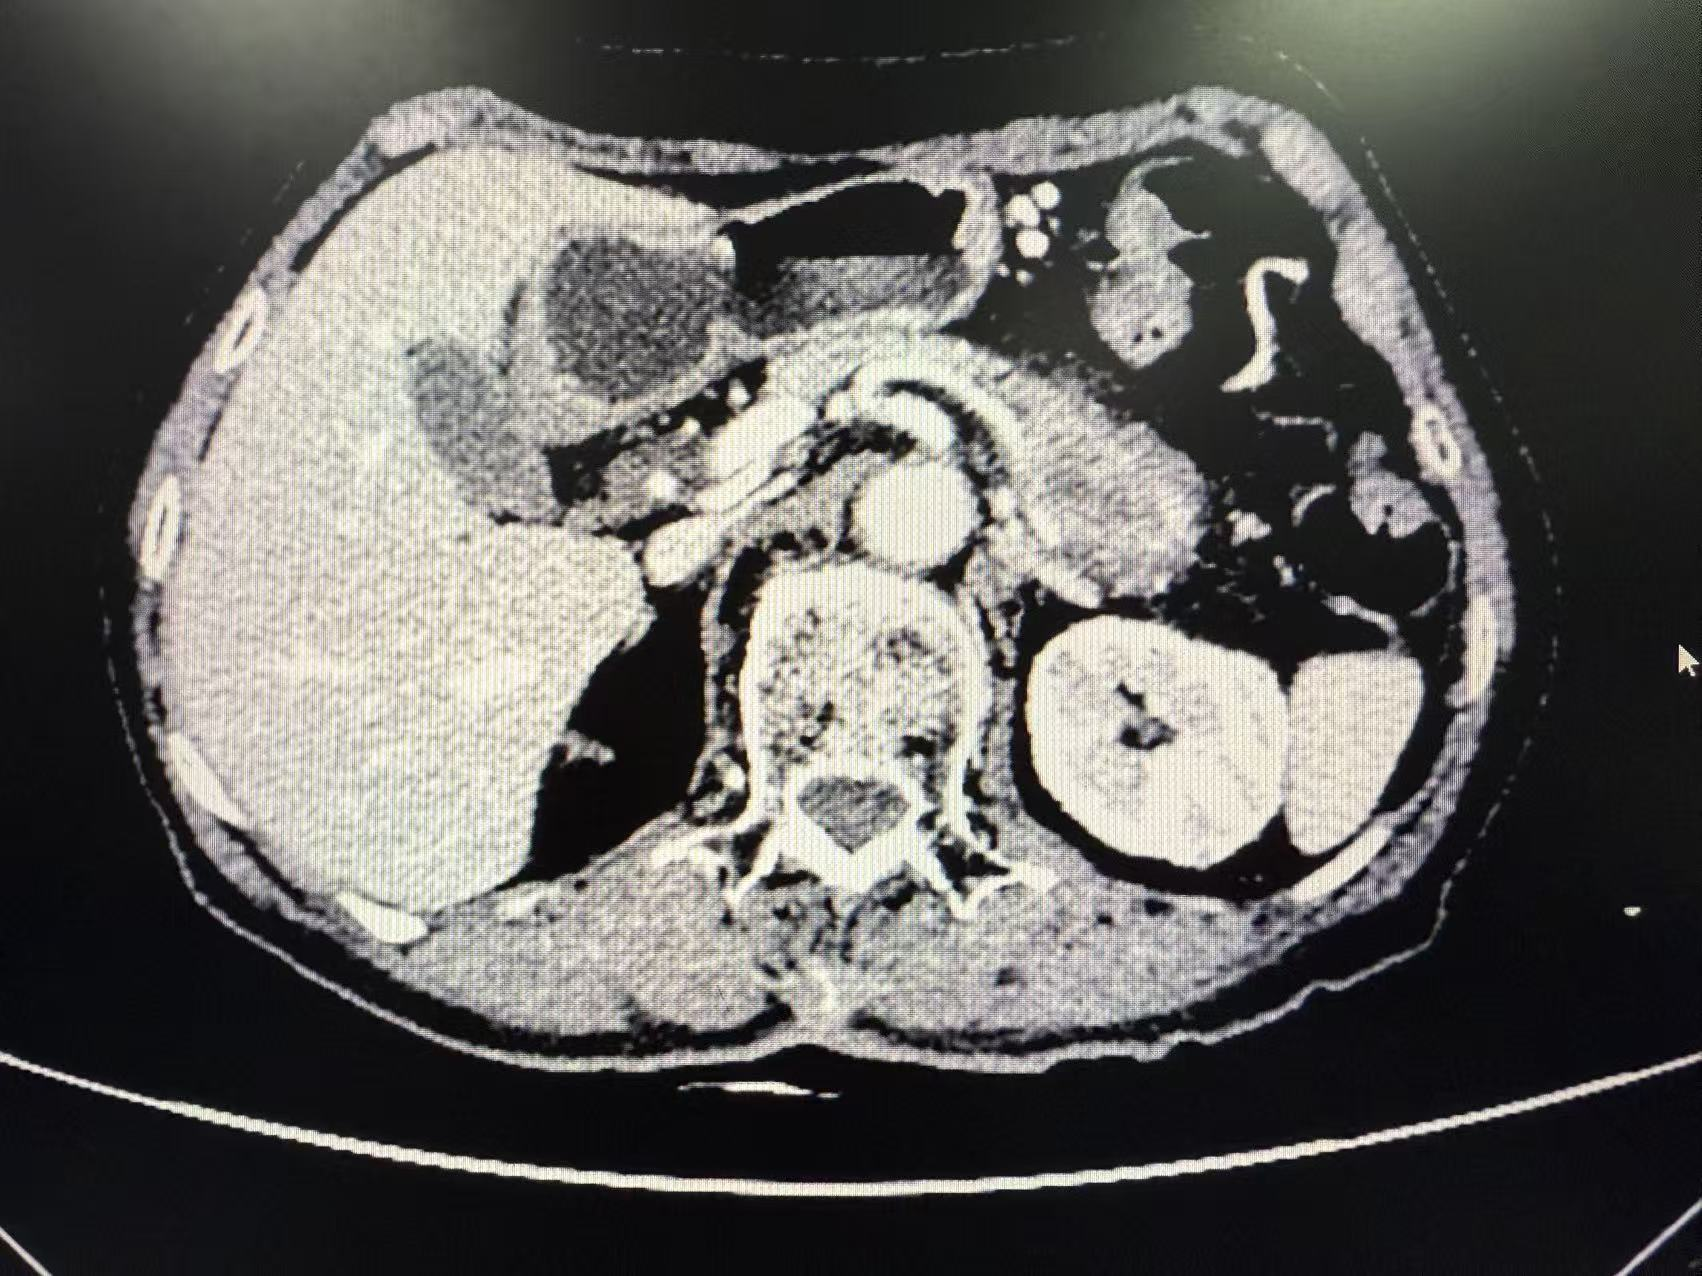

今年79岁的吕奶奶,不久前被上腹胀痛反复困扰,症状逐渐加重后,她在家人陪伴下于9月16日来到南溪山医院消化内科就诊。临床诊断考虑胰体尾癌转入肝胆胰外科。CT检查结果让所有人揪紧了心:胰腺体尾部站位4.5cmx3.7c考虑恶性肿瘤,更棘手的是肿瘤已侵犯脾动静脉。胰体尾癌的传统手术方式是胰体尾部加脾脏切除,解剖层面为胰后包膜和肾前筋膜之间,该患者肿瘤已经侵犯脾动静脉,传统手术容易导致肿瘤残留而无法做到真正的R0切除。L-RAMPS的手术难度要大于传统手术方式,因为它需要更多的后腹膜组织切除、血管裸露和淋巴结清扫,强调更深层面切除,包括肾前筋膜、肾前脂肪囊,甚至左侧肾上腺等,以期提高生存率。